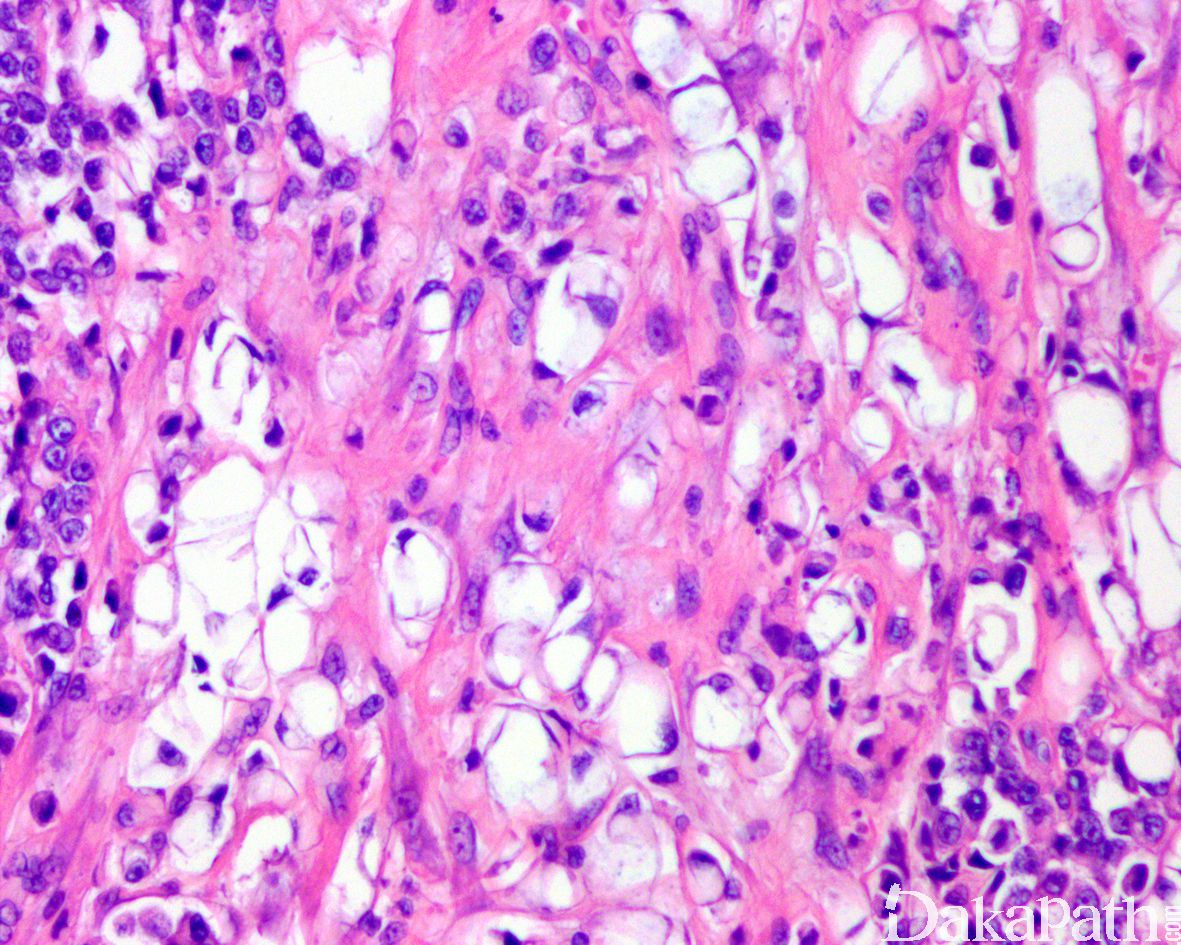

浸润性尿路上皮癌,富脂质

Infiltrating urothelial carcinoma, Lipid-rich

特征性形态学改变是存在大的脂肪母细胞样细胞,具有 1 个或多个胞浆空泡,挤压细胞核;

尿路上皮癌伴异源性 脂肪肉瘤分化 :为真性脂肪母细胞,可表达 S100 蛋白,共表达 CDK4 和 MDM2 等,FISH 检测 MDM2 扩增可资鉴别。

透明细胞尿路上皮癌 :胞浆水样透明,无脂质空泡,无核挤压的切迹,胞浆内物质 PSA 阳性。